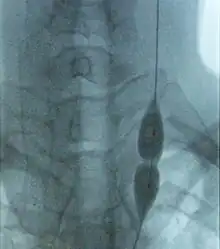

| Veins of the neck. V.jugularis interna is proposed to be stenosed or have a malformed valve in CCSVI cases. | |